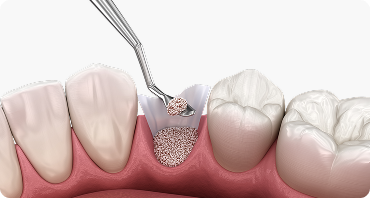

뼈이식 임플란트

임플란트에서 중요한 부분은 두꺼운 뼈와 건강한 잇몸에 있습니다.

뼈가 안 좋아 임플란트가 어려울 경우, 임플란트 식립을 위해

약해진 잇몸뼈를 이식하여 임플란트의 장기적인 수명을 향상시킵니다.

상악동 거상술 시행

부족한 잇몸뼈를 보완하여 임플란트

식립 환경을 안전하게 형성합니다.